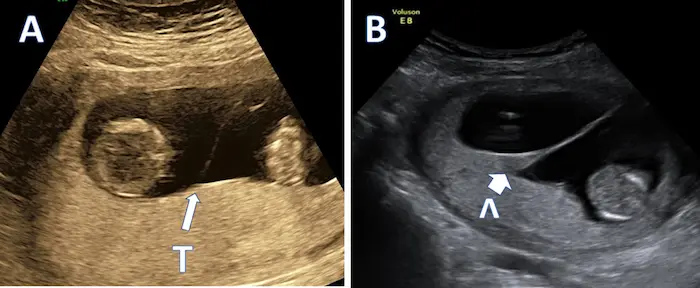

Not all twin pregnancies are the same. The early development of your twins sets the stage for their prenatal care. Your first ultrasound will be crucial in determining this.

- Monochorionic-Diamniotic (Mo-Di): The split occurs between days 4-8. Twins share a single placenta but have separate amniotic sacs. This requires closer monitoring for conditions like Twin-to-Twin Transfusion Syndrome (TTTS).

- Monochorionic-Monoamniotic (Mo-Mo): The rarest and highest-risk type, where the split occurs after day 9. Twins share both a single placenta and a single amniotic sac, risking cord entanglement. This requires extremely specialized care and very early delivery.

Why this matters: Your twins’ chorionicity (placenta number) is the most important factor guiding your prenatal care, more so than whether they are identical or fraternal. A di-di pregnancy generally has the lowest risk profile.